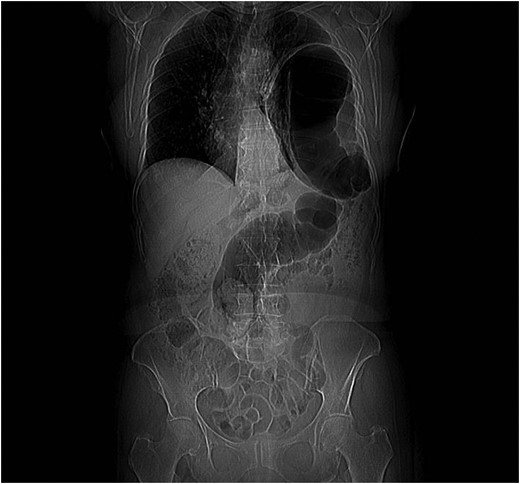

In April 2011, a 73-year-old woman with history of left-pancreatectomy and splenectomy for a neuroendocrine tumour (2009) was admitted to the emergency department with abdominal cramps, nausea, without vomit or dyspnea. Her anamnesis was negative for asthma, respiratory distress, blunt or penetrating trauma or conspicuous weight loss. Abdominal examination showed a diffusely painful protruding abdomen, without signs of peritonitis and Blumberg sign was negative. Chest radiographs (Fig. 1) showed a raised left hemidiaphragm, with bowel herniation into the lower half of the left hemi-thorax.